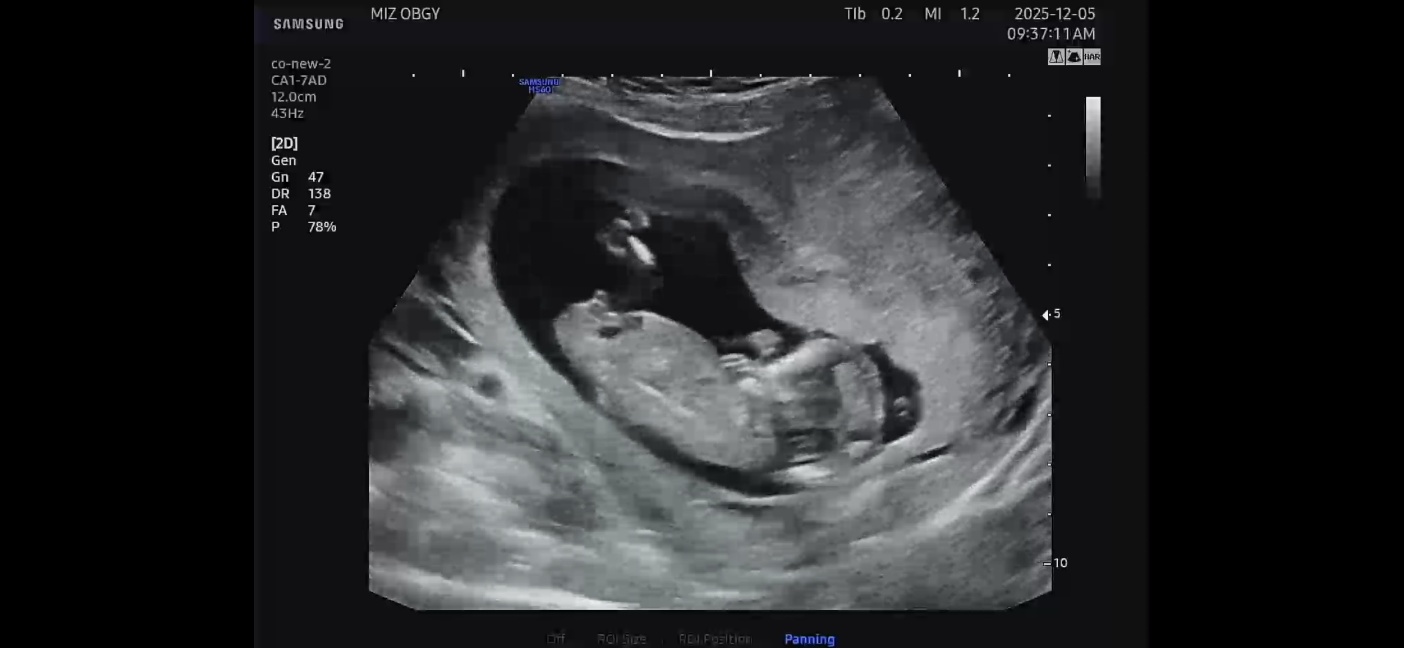

12주차 각도법 성별 궁금합니다 ㅜㅜ

각도법 성별 궁금합니다!!